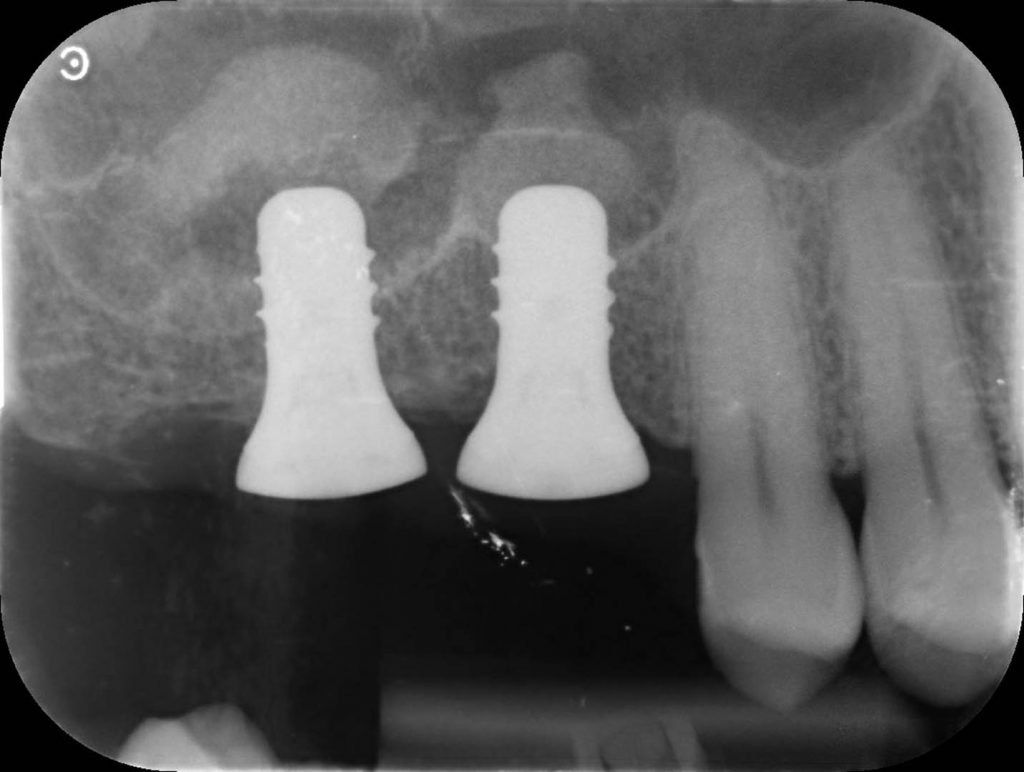

Two 8mm Straumann Wide-Neck have been inserted. After inserting a healing abutment with a height of 2 mm, a detached stitches suture was made. Good planning allowed me to be precise with the incision, and only 2 stitches have been necessary.

Pre-op and post-op CBCT have been obtained with my Carestream 8100. In addition to providing us with very defined images, this device allows performing CBCT of only three teeth. This greatly reduces the radiation dose for the patient.